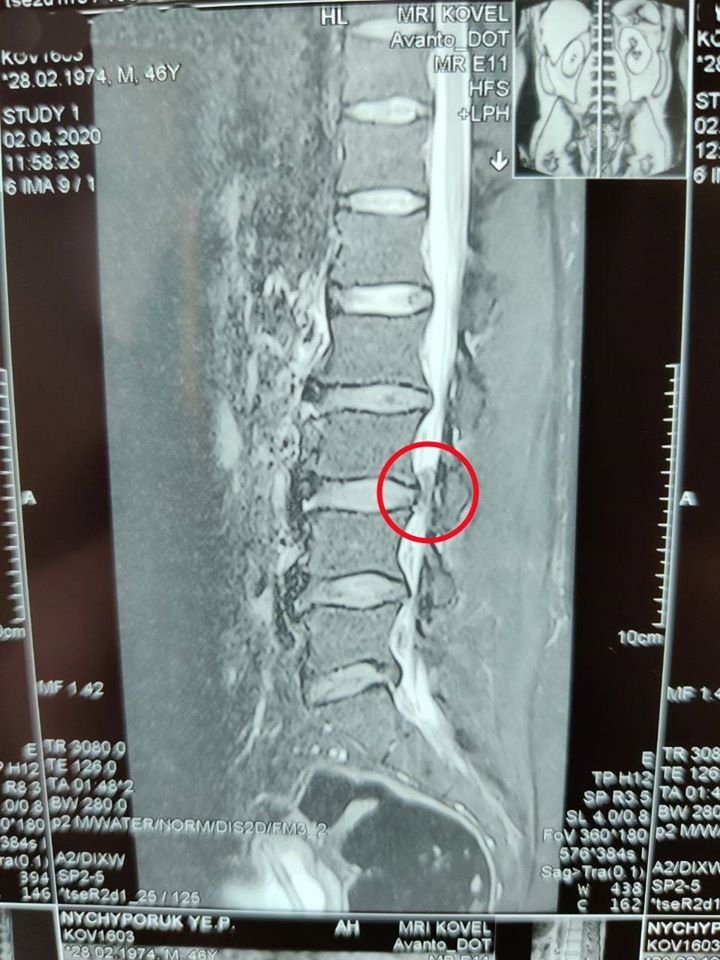

Лікарі Ковельського МТМО прооперували чоловіка, у якого діагностували секвестровану грижу L3-L4 з критичним стенозом спинномозкового каналу.

Чоловік 46 років був скерований з Камінь-Каширського району з вираженими болями в попереку, які іррадіювали в нижні кінцівки, та порушенням функції тазових органів.

Медики в ургентному порядку провели видалення секветрованої грижі справа (мікродискектомія L3-L4 справа). Наразі пацієнт почуває себе чудово і вже може вільно пересуватися.